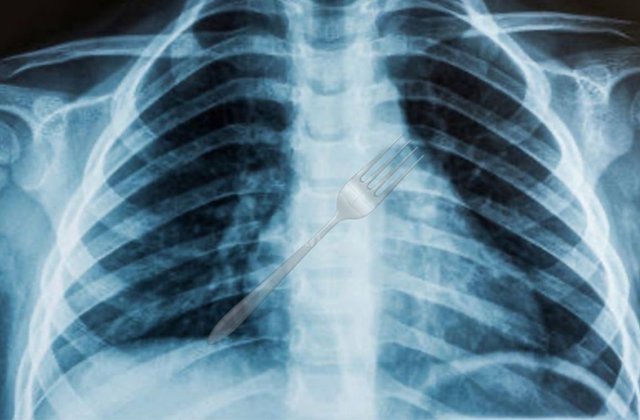

Um caso inusitado mobilizou médicos e moradores de Guanambi, no sudoeste da Bahia. Uma mulher engoliu um garfo durante uma refeição na sexta-feira (26). Vítima foi levada ao Hospital Geral de Guanambi (HGG) em estado de urgência. Exames de imagem mostraram que o utensílio ficou preso no esôfago.

Os médicos constataram que o objeto estava em posição de alto risco. Localização poderia comprometer órgãos vitais e causar perfurações internas. Profissionais decidiram pela transferência imediata da paciente. Ela seguiu para Vitória da Conquista, onde deve passar por procedimento especializado.